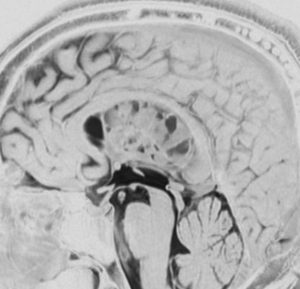

52歳の男性で,2008年に脳ドックで見つかって無症状でした。中枢性神経細胞種 central neurocytomaを疑いましたが,上衣下腫 subependymomaはまったく考慮に入れませんでした。壮年男性でしたから経過観察しました。右側は2019年,11年後のものです。徐々に増大して水頭症になり歩行障害がでてきました。

手術前の画像です。血管が豊富で大きな導出静脈がみられ,腫瘍内出血もあります。ガドリニウムでは部分的に増強されます。CISS/FIESTAの画像では,透明中核から発生したようにみえて,脳浸潤は全くありません。脳弓は腫瘍の底面にありますが,もちろん境界はっきりしません。これらもcentral neurocytomaの画像所見として捉えられるものです。

transcallosal approach 経脳梁法で亜然摘出しました。底面には脳弓があって剥離できないから全摘出はできません。病理所見は,のう胞形成を伴う線維性基質の中に楕円形の細胞が索状または小巣状に増生するものでsubependymomaと診断されました。異型は軽度で,核分裂像はなく,MIB-1染色率は1%以下のWHO grade Iの所見。EMAは細胞質にdot likeに陽性でしたがわずかであり,ependymomaとの合併腫瘍の診断には至りませんでした。

術後1年の画像です。無症状で復職できています。